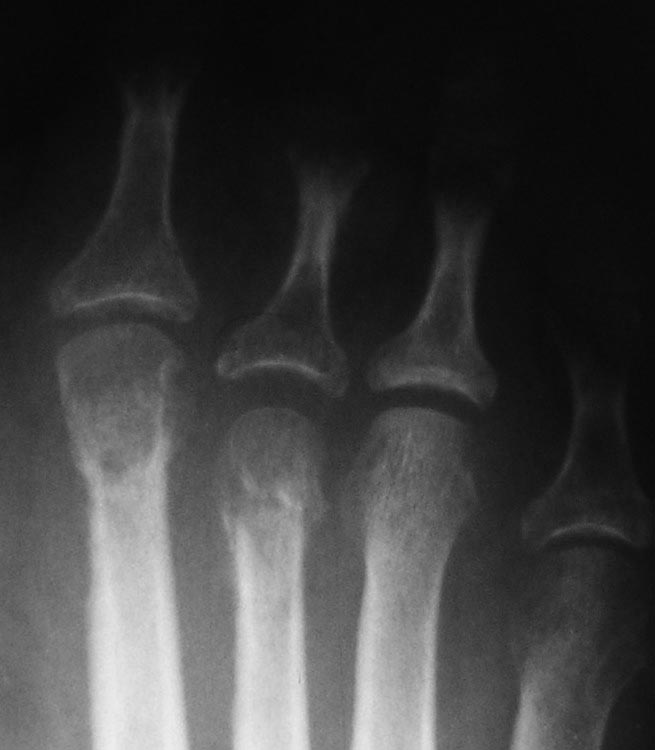

Нефиксированный Вейль значит без фиксации винтами. Заживает по тем же принципам, что и субкапитальные остеотомии в чрескожной хирургии, которые под воздействием ранней нагрузки (обувь с разгрузкой переднего отдела стопы здесь не нужна) находят свое идеальное положение. Только нужно учитывать, что рентгенологическое сращение может больше времени занять и не пугаться этого. На рентгенограммах пример такого Вейля 7-летней давности. Формула, конечно, не соблюдена, но вывихи вправлены без резекций головок.Поскольку уже давно такие операции делаю чрескожно, более свежих примеров нет.